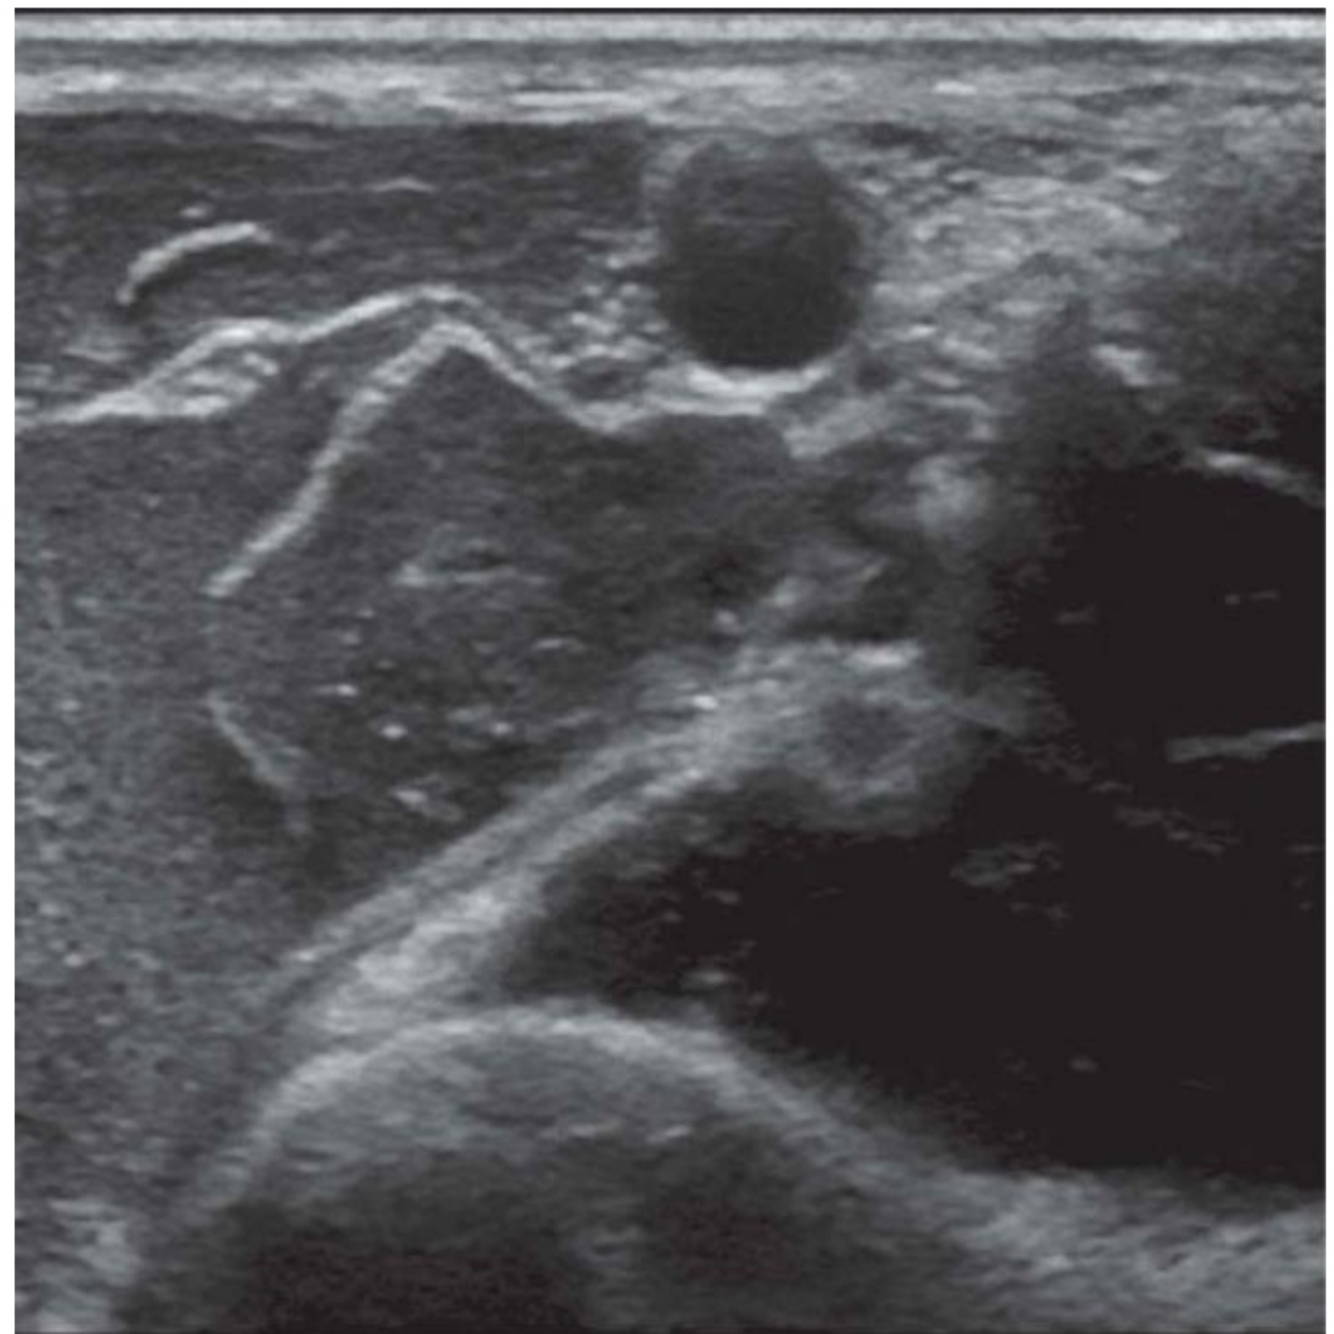

Look at the ultrasound image in Figure 3.1a and name the structures.

A

○ Median, ulnar, and radial nerves are seen scattered around the axillary artery with the tissue sheath.

○ The musculocutaneous nerve is seen between the biceps and coracobrachialis away from the rest of the brachial plexus.

○ The axillary vein is compressed leading to the possibility of accidental intravascular injection of local anaesthetic

• Ultrasound probe positioned with short axis to arm just distal to pectoralis major insertion

• Aim to achieve local anaesthetic spread around the axillary artery covering median, ulnar, and radial nerve and a separate injection to cover the musculocutaneous nerve

• Total volume of local anaesthetic 20–25 mls of 0.25% L – Bupivacaine (5–7 mL around each nerve)